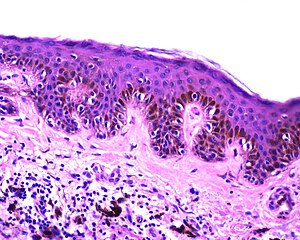

Simple lentigo. H&E stain. (WC) | |

| LM | melanocytes in epidermis only - hyperpigmentation; no melanocytic nests; +/-mild/moderate elongation of the rete ridges |

- Melanocytes in epidermis only.

- Melanocytes basally located (normal location) with hyperpigmentation.

- No melanocytic nests.

- +/-Mild/moderate elongation of the rete ridges.[6]

The sections show skin with increased numbers of small pigmented melanocytes at the dermal-epidermal junction. The rete ridges are mildly elongated. No solar damage is apparent. No dermal melanocytes are identified. No melanocytic nests are identified. No nuclear atypia is apparent.